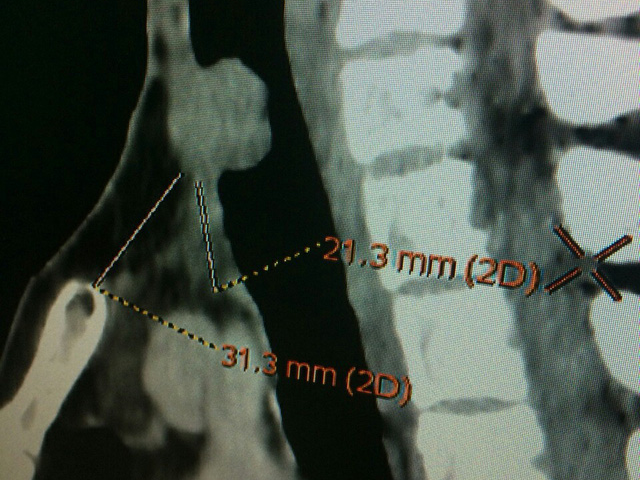

| Thử nghiệm tế bào miễn dịch điều trị ung thư. (ảnh minh hoạ). |